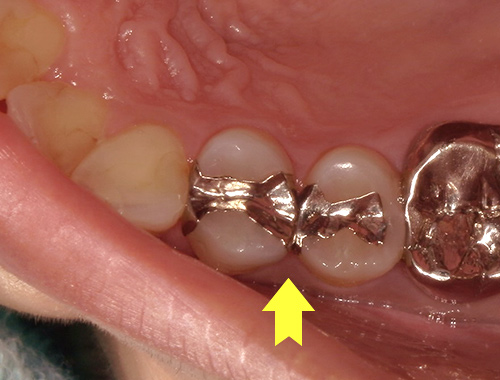

保険の詰め物から

白くて強度の強いジルコニアインレー(自費治療)に変更

保険診療で使用されていた金属の詰め物(いわゆる銀歯)を、白くて自然な見た目のセラミック(ジルコニア)に変更した症例です。金属の詰め物は強度に優れている一方、笑ったときや口を開けたときに目立ちやすく、長い年月が経つと金属成分が溶け出して歯ぐきが黒ずんで見えることがあります。

それに対し、セラミックの詰め物は見た目がとても自然で、天然歯とほとんど見分けがつかない仕上がりが可能です。金属を一切使用しないため、金属アレルギーの心配がなく、身体にも優しい素材です。

今回使用したジルコニアは、セラミックの中でも特に強度に優れており、歯を薄く削って作製できるという利点があります。一方で、オールセラミックに比べると透明感はやや出にくい素材です。患者さまから「なるべく歯を削らず、強度も確保したい」とのご要望があったため、このジルコニア素材を選択しました。精密に作製されるため適合性にも優れており、しっかりとフィットして虫歯の再発を防ぐ効果も期待できます。

写真では、治療前後の違いをご覧いただけます。黄色い矢印の部分が、実際にセラミックに置き換えた箇所です。治療後は口元の印象が明るくなり、患者さまにも大変ご満足いただけました。

治療期間通院3回(むし歯治療、型取り、セット)、約2週間程度

費用目安税込77,000円×2